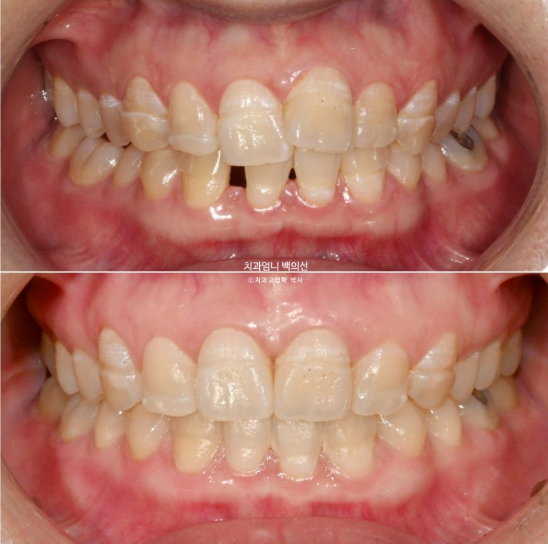

23년 10월 교정치료를 위해 찾아오신 30대 환자분입니다.

23.10

아래 앞니 사이에 벌어진 공간이 있고 위 앞니는 덧니가 있습니다.

앞니에 울퉁불퉁한 띠가 있는데 법랑질저형성증 입니다.

앞니가 튀어나와 돌출도 있습니다.

아래 앞니 4개 중 2개가 없습니다.

태어날때부터 없는 경우를 선천적 결손이라고 합니다.

이제 전후 비교 보겠습니다. 총 치료기간은 1년 8개월입니다.

23.10~25.06

임플란트 없이 교정만으로 깔끔하게 마무리된 모습입니다.

앞니 덧니와 돌출이 해소가 되었습니다.